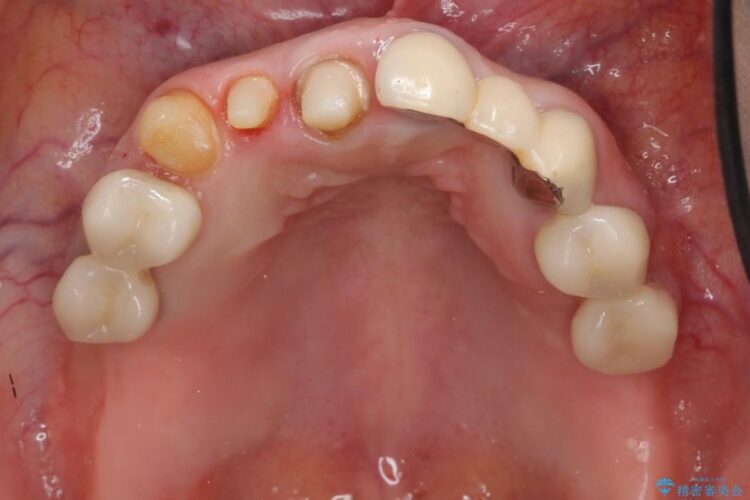

上顎右側の前歯2本のかぶせ物部分の再治療と犬歯に発生していた虫歯治療を主訴に来院されました。

前歯のかぶせ物に関しましては、内面が金属で覆われているため歯茎にその色が透けて見えるという審美的な問題と、かぶせ物と歯の境界が不適合であるという問題がありました。

犬歯の虫歯につきましては、何度も詰め物治療が繰り返されている痕跡があり今回虫歯を取りきるにあたり歯の強度に不安が残るため前歯と同時にかぶせ物の治療をしていくことを計画しました。